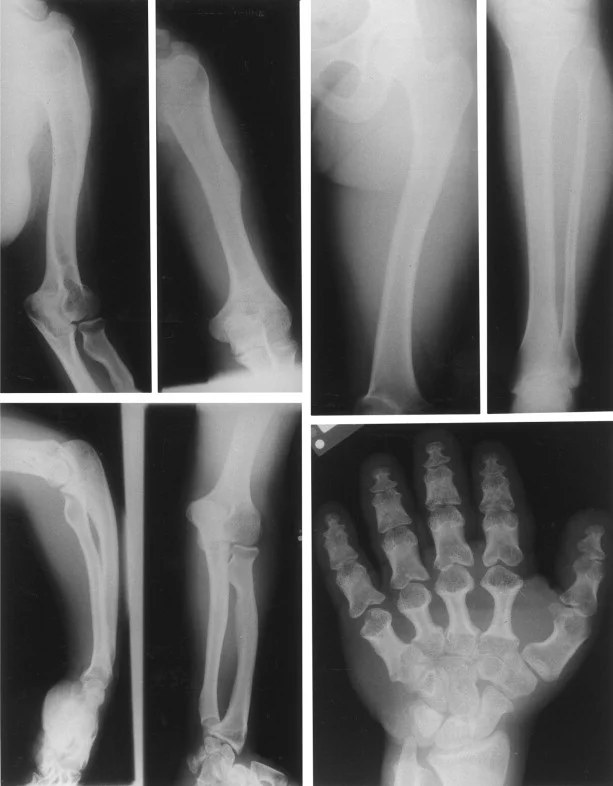

مطالعات تخصصی اشعه ایکس ممکن است رشد غیر طبیعی و همجوشی زودرس نواحی را تأیید کند که در آن شفت (دیافیز) برخی از استخوانهای بلند (یعنی استخوانهای بازوها و پاها) به انتهای رشد آنها (اپیفیز) میرسند. علاوه بر این، آنها ممکن است همجوشی غیرطبیعی انتهای در حال رشد استخوانها را در انگشتان، انگشتان پا، دستها و پاها (مانند فالانژها، متاکارپالها، متاتارسها) نشان دهند.

چنین مطالعاتی همچنین ممکن است وجود و یا میزان ناهنجاریهای استخوانی ناشی از آن را تأیید کند (مانند استخوان زند کوتاه و رادیوس، سر رادیال دررفته یا سابلوکس، فالانژهای کوتاه و بدشکل و غیره) و همچنین سایر ناهنجاریهای اسکلتی که ممکن است با آکرومزولیک همراه باشد. دیسپلازی (مانند ناهنجاریهای مهره ای و در نتیجه کیفوز پایین قفسه سینه و یا هیپرلوردوز کمری، ایلیا هیپوپلاستیک و غیره).